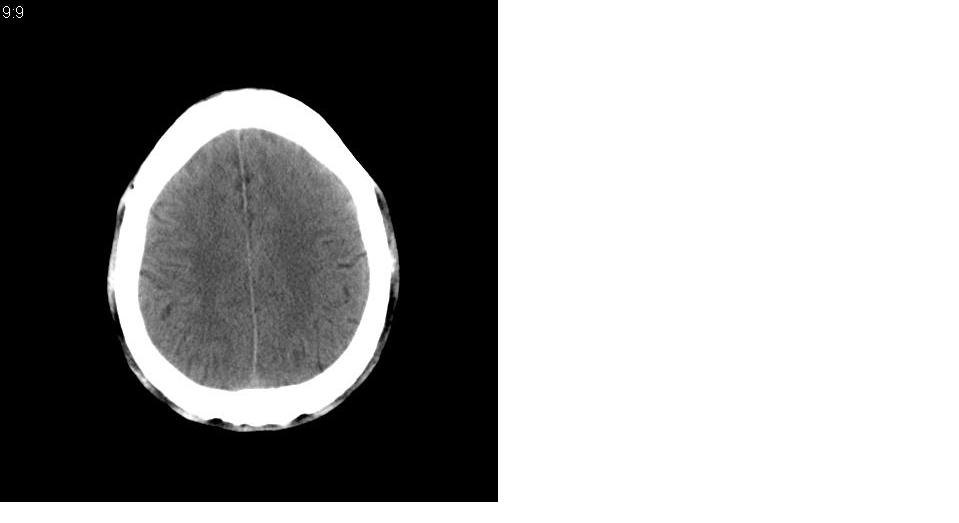

以下是引用tianhep在2007-5-9 19:53:00的发言:[br]这个部位多为苍白球钙化,苍白球钙化往往双侧对称。有外伤史而无症状。首先考虑为苍白球钙化。短期内复查一次就可。

以下是引用狙击手在2007-5-9 19:52:00的发言:[br]病灶边界模糊,外周无水肿带,无占位效应,无任何不适,考虑钙化。

以下是引用gyh6308在2007-5-9 21:10:00的发言:[br]这种病例我见过,是脑血管畸形所致的钙化,做cta可观察